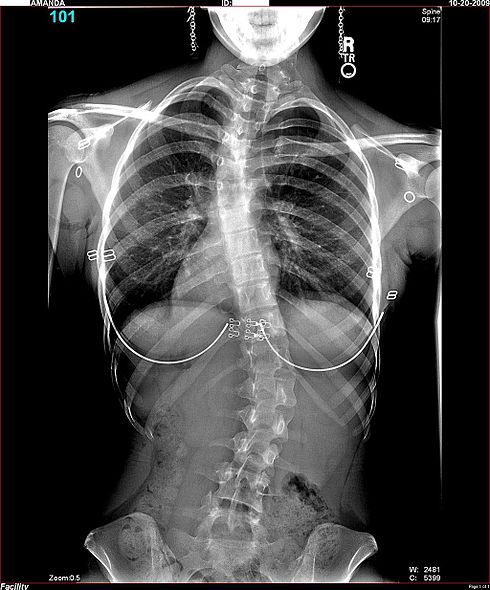

TRAUMATOLOGÍA Y ORTOPEDIA

La Traumatología y Ortopedia, es una especialidad de la medicina, dedicada específicamente a las enfermedades del sistema musculo-esquelético.

• Problemas del desarrollo de los huesos

- Malformaciones congénitas

- Luxación congénita de caderas

- Pie equino-varo, etc.

• Lesiones

- Fracturas

- Lesiones musculares

- Lesiones articulares

- Lesiones meniscales, etc.

Enfermedades infecciosas de los huesos

Tumoraciones de los huesos y músculos

Enfermedades reumáticas

• Enfermedades degenerativas por desgaste (secundarias a lesiones antiguas no tratadas adecuadamente o causadas por sobrecarga en el trabajo, por obesidad, etc.)

• Deformidades de extremidades

- Genu valgo

- Genu varo

- Columna (escoliosis)

- Juanetes